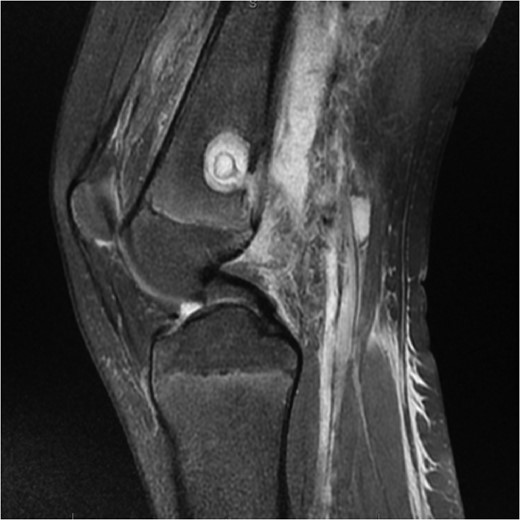

Coronal slice images of presenting MRI, displaying the brodie's abscess and collection.